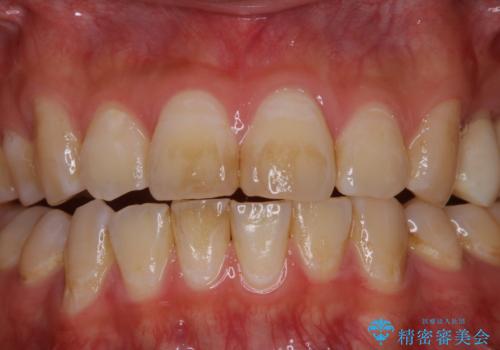

紅茶による着色を1日できれいに

- 紅茶を頻繁に飲むため、歯の黄ばみが気になるとのことでした。PMTC60分コースを行いました。